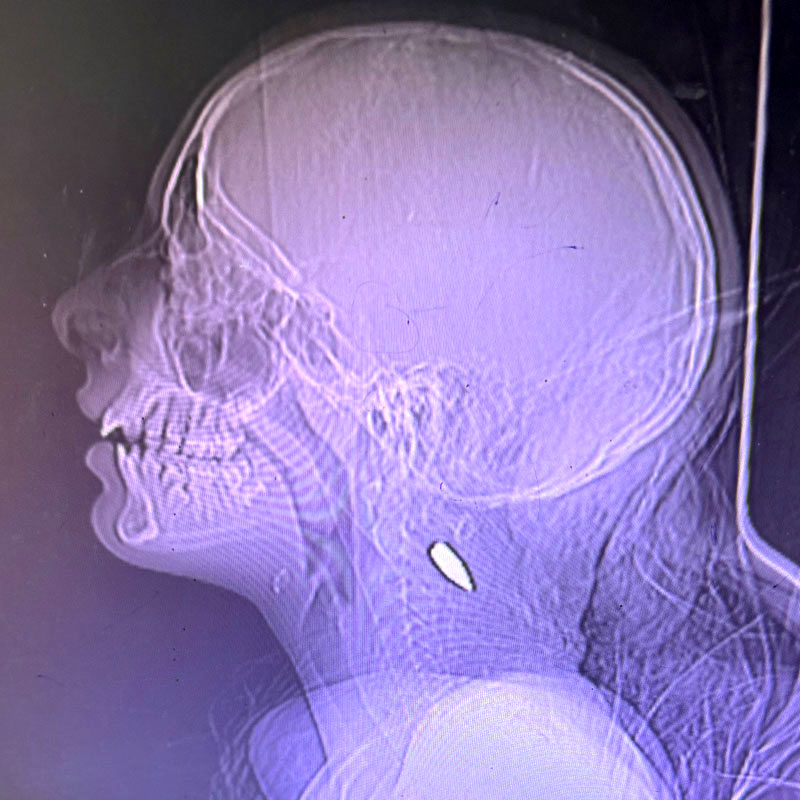

یکی از پزشکان داوطلب حاضر در غزه گفته است: در دوران فعالیت من به عنوان جراح تروما در غزه، تقریباً هر روز شاهد کودکانی بودم که به سر یا سینه‌شان شلیک شده بود و متأسفانه بیشتر آن‌ها جان خود را از دست دادند. پس از بازگشت به خانه، از یک پزشک دیگر شنیدم که این الگوی خشونت علیه کودکان در بیمارستان‌های مختلف غزه به طرز شوکه‌کننده‌ای رایج بوده است.

من به عنوان جراح تروما در غزه از ۲۵ مارس تا ۸ آوریل کار کردم. من به عنوان داوطلب در اوکراین و هائیتی هم کار کرده‌ام و در فلینت میشیگان بزرگ شدم. خشونت دیده‌ام و در مناطق جنگی کار کرده‌ام. اما در میان بسیاری از چیزهایی که در کار کردن در بیمارستانی در غزه به چشمم آمد، یک مورد به شدت مرا تحت تأثیر قرار داد: تقریباً هر روز که آنجا بودم، یک کودک خردسال جدید را می‌دیدم که به سر یا سینه‌اش شلیک شده بود و تقریباً همه آن‌ها جان می‌باختند. در مجموع، سیزده کودک. در آن زمان، فکر می‌کردم که این باید کار یک سرباز به‌خصوص و سادیستی باشد که در نزدیکی آنجا مستقر است. اما بعد از بازگشت به خانه، با یک پزشک اورژانس آشنا شدم که دو ماه قبل از من در بیمارستانی دیگر در غزه کار کرده بود. به او گفتم: «نمی‌توانستم باور کنم که تعداد زیادی از کودکانی که به سرشان شلیک شده بودند را دیدم.» در کمال تعجب، او پاسخ داد: «بله، من هم همین‌طور. هر روز.» اطلاعات گسترده‌ای درباره میزان ویرانی‌ها در غزه از داده‌های ماهواره‌ای، سازمان‌های بشردوستانه و وزارت بهداشت غزه به دست آمده است. با این حال، اسرائیل اجازه ورود خبرنگاران یا محققان حقوق بشر به غزه را نمی‌دهد، به‌جز تعداد بسیار کمی از سفرهایی که گزارشگران را همراه با ارتش اسرائیل به آنجا می‌روند. علاوه بر آن داستان‌های خبرنگاران فلسطینی در غزه، علی‌رغم خطرات زیادی که در گزارش‌دهی متحمل می‌شوند، به اندازه کافی خوانده نشده است. اما یک گروه از ناظران مستقل هستند که این جنگ را روز به روز از نزدیک دیده‌اند: کارکنان داوطلب بهداشت و درمان. از طریق ارتباطات شخصی در جامعه پزشکی و جستجوی فراوان آنلاین، توانستم با کارکنان بهداشتی-درمانی آمریکایی که از ۷ اکتبر ۲۰۲۳ در غزه خدمت کرده‌اند، ارتباط برقرار کنم. بسیاری از آن‌ها پیوندهای خانوادگی یا مذهبی با خاورمیانه دارند. دیگران، مانند من، این پیوندها را ندارند، اما به دلایل مختلف احساس وظیفه کرده‌اند که به صورت داوطلبانه در غزه خدمت کنند. با استفاده از پرسش‌هایی که بر اساس مشاهدات شخصی و گفتگوهایم با پزشکان و پرستاران همکارم طراحی کردم، با همکاری تیم نظرخواهی نیویورک‌تایمز، از ۶۵ نفر از کارکنان بهداشت و درمان درباره تجربیاتشان در غزه نظرسنجی کردیم. پنجاه و هفت نفر، از جمله خودم، مایل بودند تجربیاتشان را به صورت علنی به اشتراک بگذارند. هشت نفر دیگر به صورت ناشناس شرکت کردند، یا به دلیل داشتن خانواده در غزه یا کرانه باختری، یا به دلیل ترس از انتقام‌جویی در محیط کار. این چیزی است که ما دیدیم:

۴۴ پزشک، پرستار و امدادگر شاهد موارد متعددی از کودکان هنوز به دوران نوجوانی نرسیده که در غزه به سر یا سینه شلیک شده بودند.

"یک شب در بخش اورژانس، طی چهار ساعت، شش کودک بین ۵ تا ۱۲ سال را دیدم که همه‌شان یک زخم گلوله به جمجمه داشتند."

"چندین کودک را دیدم با زخم‌های ناشی از گلوله‌های پرسرعت، که همگی به سر و سینه‌شان شلیک شده بود."

"تیم ما از حدود چهار یا پنج کودک، بین ۵ تا ۸ ساله، مراقبت می‌کرد که همگی یک تیر به سرشان شلیک شده بود. همه آن‌ها همزمان به اورژانس آمدند. همه آن‌ها جان باختند."

"یک روز، در اورژانس، یک کودک ۳ ساله و یک کودک ۵ ساله را دیدم که هر کدام یک گلوله به سرشان اصابت کرده بود. وقتی پرسیدیم چه اتفاقی افتاده است، پدر و برادر گفتند که به آن‌ها گفته شده بود اسرائیل در حال عقب‌نشینی از خان‌یونس است. بنابراین، آن‌ها برگشتند تا ببینند آیا چیزی از خانه‌شان باقی مانده است یا نه. آن‌ها گفتند یک تک‌تیرانداز منتظر بود و به هر دو کودک شلیک کرد."

"من دختر ۱۸ ماهه‌ای را دیدم که یک زخم گلوله در سر داشت."

"من کودکان زیادی را دیدم. بر اساس تجربه من، اغلب جراحت ناشی از شلیک گلوله به سر آن‌ها بود. بسیاری از این کودکان دچار آسیب‌های مغزی دائمی و غیرقابل درمان شده بودند. تقریباً هر روز شاهد بودیم که کودکان با جراحت ناشی از گلوله به سر وارد بیمارستان می‌شدند."